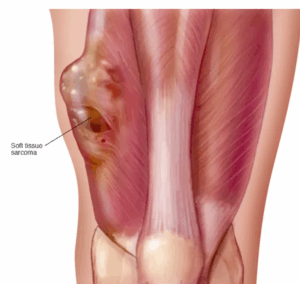

Soft tissue sarcoma

Soft tissue sarcoma is a rare type of cancer that starts as a growth of cells in the body's soft tissues. The soft tissues connect, support and surround other body structures. Soft tissues include muscle, fat, blood vessels, nerves, tendons and linings of the joints.